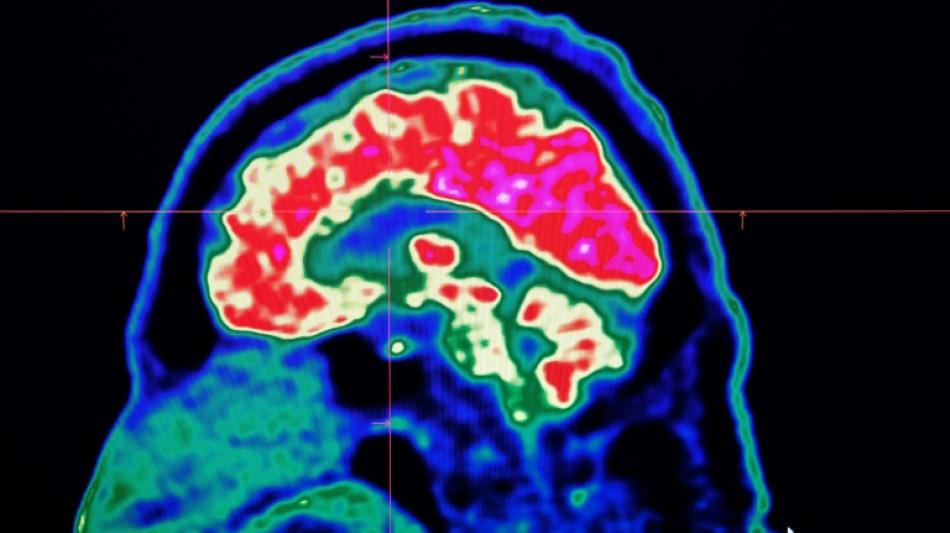

Surging nervous system disorders now top cause of illness: study / Photo: Fred TANNEAU - AFP/File

Conditions affecting the nervous system -- such as strokes, migraines and dementia -- have surged past heart disease to become the leading cause of ill health worldwide, a major new analysis said on Friday.

More than 3.4 billion people -- 43 percent of the global population -- experienced a neurological condition in 2021, far more than had previously been thought, the analysis found.

Lead study author Jaimie Steinmetz of the IHME said the results showed that nervous system conditions are now "the world's leading cause of overall disease burden".

Cases of these conditions have soared by 59 percent in the last three decades, she said, with the increase mainly driven by the fact that the world's population was ageing and growing fast.

The researchers looked at how 37 different neurological conditions affected ill health, disability and premature death across 204 countries and territories from 1990 to 2021.

This data was used to estimate how many years of healthy life were lost to each condition, called disability-adjusted life years (DALYs).

More than 443 million years of healthy life were lost to nervous system disorders globally in 2021, an 18-percent increase from 1990, the study found.

Stroke, which was previously counted as a heart disease, was by far the worst neurological condition analysed, accounting for 160 million years of healthy life lost.

It was followed by a form of brain damage called neonatal encephalopathy, migraine, dementia including Alzheimer's disease, nerve damage from diabetes, meningitis and epilepsy.

Cognitive impairment from Covid-19 ranked 20th.

The main reason that nervous system conditions surpassed cardiovascular disease in the latest analysis was a recent World Health Organization classification change that moved stroke into the neurological category, Steinmetz told AFP.

More than 11 million people died from the 37 neurological conditions in 2021, according to the study in The Lancet Neurology journal.

The most common neurological disorders were tension headaches and migraines.

The quickest-growing condition was nerve damage called diabetic neuropathy from soaring cases of diabetes.

They called for much more to be done to prevent, treat and rehabilitate the disorders, which disproportionately affect poorer countries.

"The worldwide neurological burden is growing very fast and will put even more pressure on health systems in the coming decades," warned study co-author Valery Feigin.